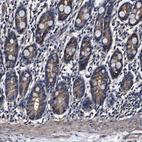

Immunohistochemical staining of human kidney shows moderate cytoplasmic positivity in cells in tubules.